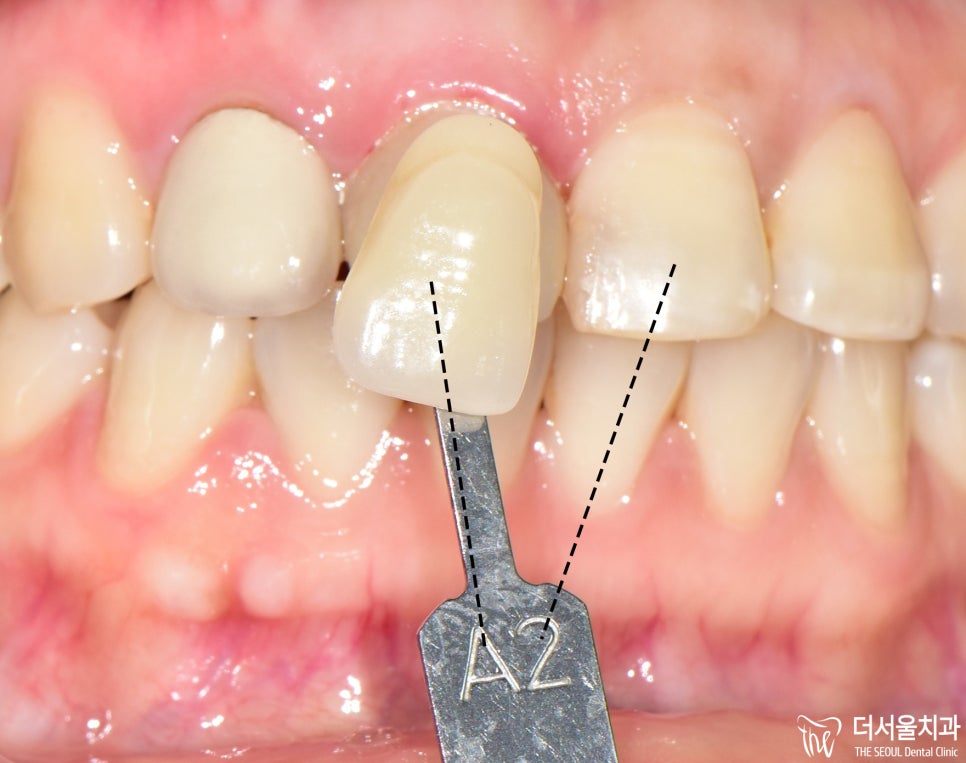

그 전에 shade taking 을 거쳐서

양 옆에 있는 치아들과 색조가

어우러질 수 있도록 합니다.

이 과정은 은근히 중요합니다.

또 보면, 교합면에서 일반 치아와

크라운과 색조 차이가 꽤 많이

나는것을 볼 수 있죠?

사진에는 크게 느껴지지 않으나

실제로 보면 더 많이 티 납니다.